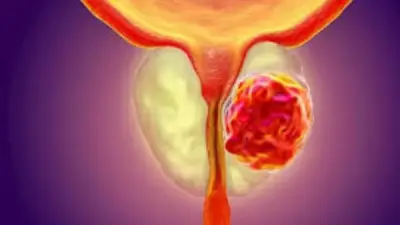

علامات سرطان البروستاتا التحذيرية

تعرف على أعراض سرطان البروستاتا المبكرة والمتقدمة، وأهمية الفحوصات المبكرة في اكتشاف المرض قبل ظهور العلامات.